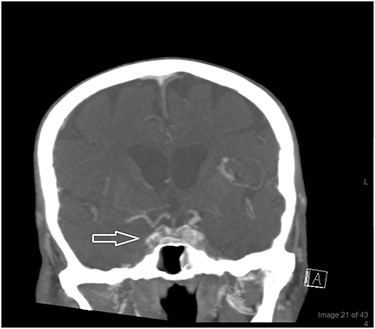

On examination, the patient was found to be afebrile, confused, generally weak and incoherent. Complete ophthalmoplegia despite no marked signs of inflammation with non-reactive pupils and no view of the posterior fundus were marked (Fig. 1). A reduction in right visual acuity from ‘counting fingers’ to ‘light perception’ was noted. An ophthalmic B scan revealed infiltration of the right globe. A computed tomography (CT) scan of the orbit and brain revealed signs of cavernous sinus thrombosis versus orbital cellulitis (Fig. 2A and B).

(A, B) A CT scan of the orbit and brain revealed soft tissue swelling in the pre-septal area (white arrow) and partial opacification of the right nasal cavity (A). The swelling extended to the lateral aspect of the anterior portion of the right zygomatic arch (white arrow; B).